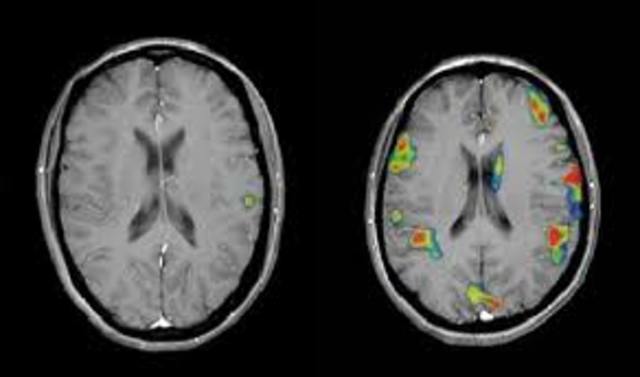

• Resonancia magnética funcional (fMRI).

Resonancia magnética funcional (fMRI).

Década en la que la neuro-imaginería da el salto y surge la resonancia magnética funcional (fMRI).